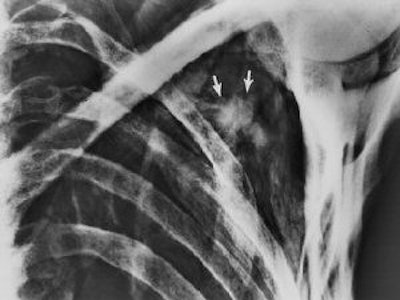

![]() |

| CT image shows the injury (x-x) and the head of the arrow (*). Figure published in: JArcheol Sci, in press, Pernter P., Gostner P., Egarter Vigl E., Rühli, F. J., "Radiologic proof for the Iceman's cause of death (ca 5300 BP), Copyright Elsevier. Image courtesy of Dr. Frank Rühli and the University of Zurich, Switzerland. |

"It seems most likely that (the arrowhead) lacerated the subclavian artery. By removing the shaft of the arrow perimortem, its head must have been slightly retracted to the actual position where the barbs caught in the tissue and, eventually, the arrowhead separated from the now missing shaft," the group wrote. "In the surrounding soft tissue one can see linear air incorporations as well as multiple irregular partially confluent densities (-80 HU), with the latter likely representing a hematoma. It spreads dorsocaudally between the ribs and the scapula, and also into the shooting channel toward the subcutaneous soft tissues" (Journal of Archaeological Science, March 15, 2007).